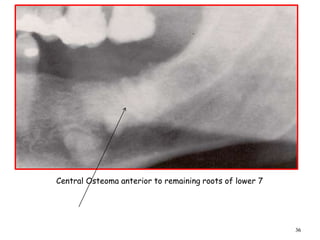

Central Osteoma anterior to remaining roots of lower 7